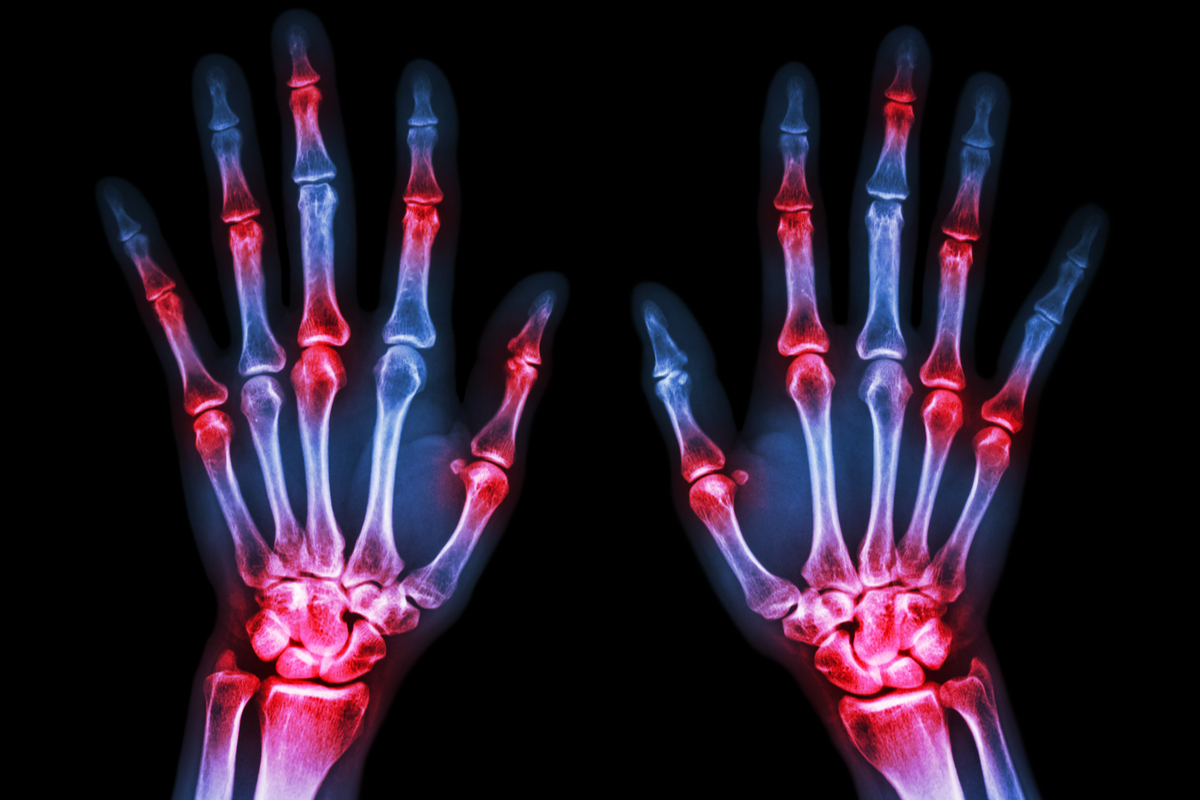

Arthritis Definition Arthralgia . Arthritis is extremely common, especially in people older than 50. Arthralgia with sudden joint pain may be caused by an injury, while arthralgia that develops and worsens over time may be due to. It's easy to confuse arthralgia with arthritis, but it's worth noting that arthralgia is an individual symptom, whereas arthritis is a health condition that occurs due to joint pain and. Arthralgia is a term used to describe aching or pain in one or more of the joints in the body. It causes joint pain, stiffness and inflammation. Your provider will help you. The main symptoms of arthritis are joint pain and stiffness, which typically worsen with age. Among its many causes are overuse, sprains, injury, gout, tendonitis and a number of infectious diseases, including rheumatic. [1] arthritis is not synonymous. Arthritis is the swelling and tenderness of one or more joints.